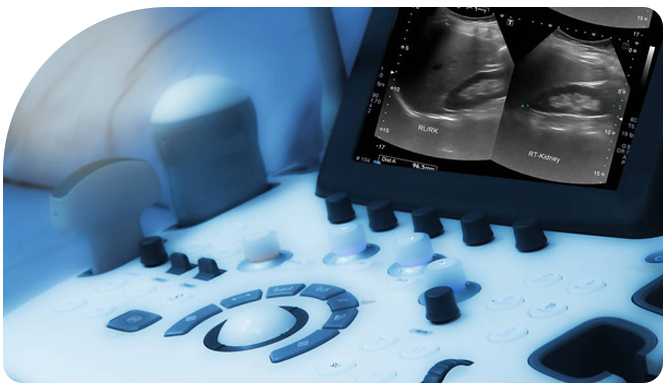

Ultrasonido Gineco-Obstétrico

Este estudio permite la visualización en detalle de los órganos reproductores y el desarrollo fetal, ofreciendo información valiosa para el diagnóstico, el seguimiento y la planificación del tratamiento.

Experiencia médica en procedimientos de ultrasonido para un monitoreo ginecológico preciso y confiable.

Ultrasonido Pélvico

Estudio no invasivo que visualiza el útero, cuello uterino, trompas de Falopio, ovarios y vagina para detectar alteraciones de salud reproductiva.

Ultrasonido Vaginal

Examen especializado que captura imágenes precisas del útero, ovarios y cuello uterino, útil para el seguimiento y/o el diagóstico.